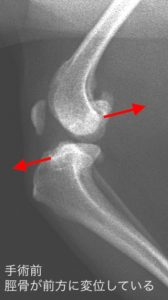

脛骨のズレや関節液の貯留を検出します。

前十字靭帯は脛骨が前方へ行くのを制限する靭帯です。

その靭帯が損傷する(①)ので脛骨が前に飛び出たように(②)なります。

多くのケースで図のように半月板が大腿骨と脛骨に挟まれて損傷します(③)。